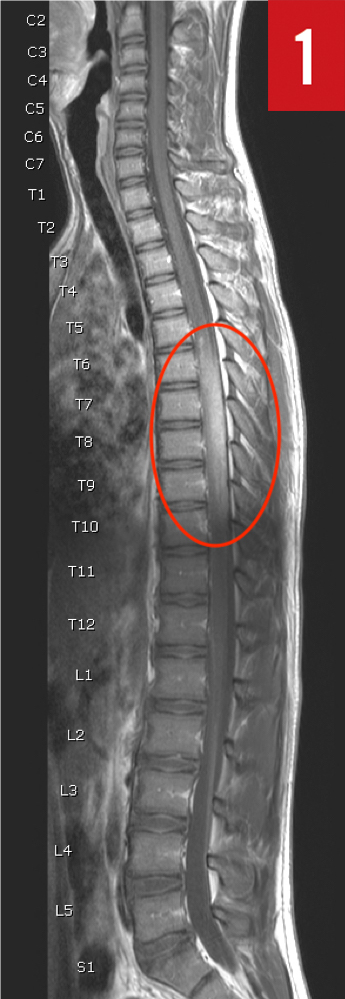

Diagnostic tests. Laboratory test results included a normal complete blood cell count, electrolyte levels, prothrombin time, partial thromboplastin time, erythrocyte sedimentation rate, C-reactive protein level, and urinalysis. A thoracolumbar spinal radiograph was obtained, the findings of which were unremarkable. Magnetic resonance imaging (MRI) of the brain and spine showed an intramedullary lesion within the thoracic cord spanning T6 through T10, resulting in effacement of the dorsal and ventral cerebrospinal fluid column (Figure 1).

Figure 1. MRI of the spine demonstrated an intramedullary lesion spanning T6 through T10 (circle).